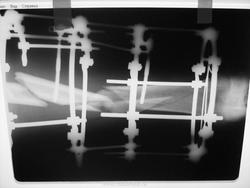

от 05.10.2012 после первой операции (20.09.2012)  после подкруток и только один

Далее три снимка от 11.10.2012 после очередных покруток

Далее от 22.10.2012 тут же после 2-ой операции (было помню два снимка, нашелся один )

Вот еще снимки от 08.02.2013

snimki_002..jpgsnimki_004..jpg

Знаете ли, эта ситуация крупнооскольчатого перелома бедра, должна быть полностью под контролем травмотолога.

Мне кажется, Он выстроил осколки по оси кости, и это- главное. Сомкнуть их не представляется возможным без открытого остеосинтеза.  Ждите консолидации. Под Аппаратом Илизарова срощение наступает быстро.